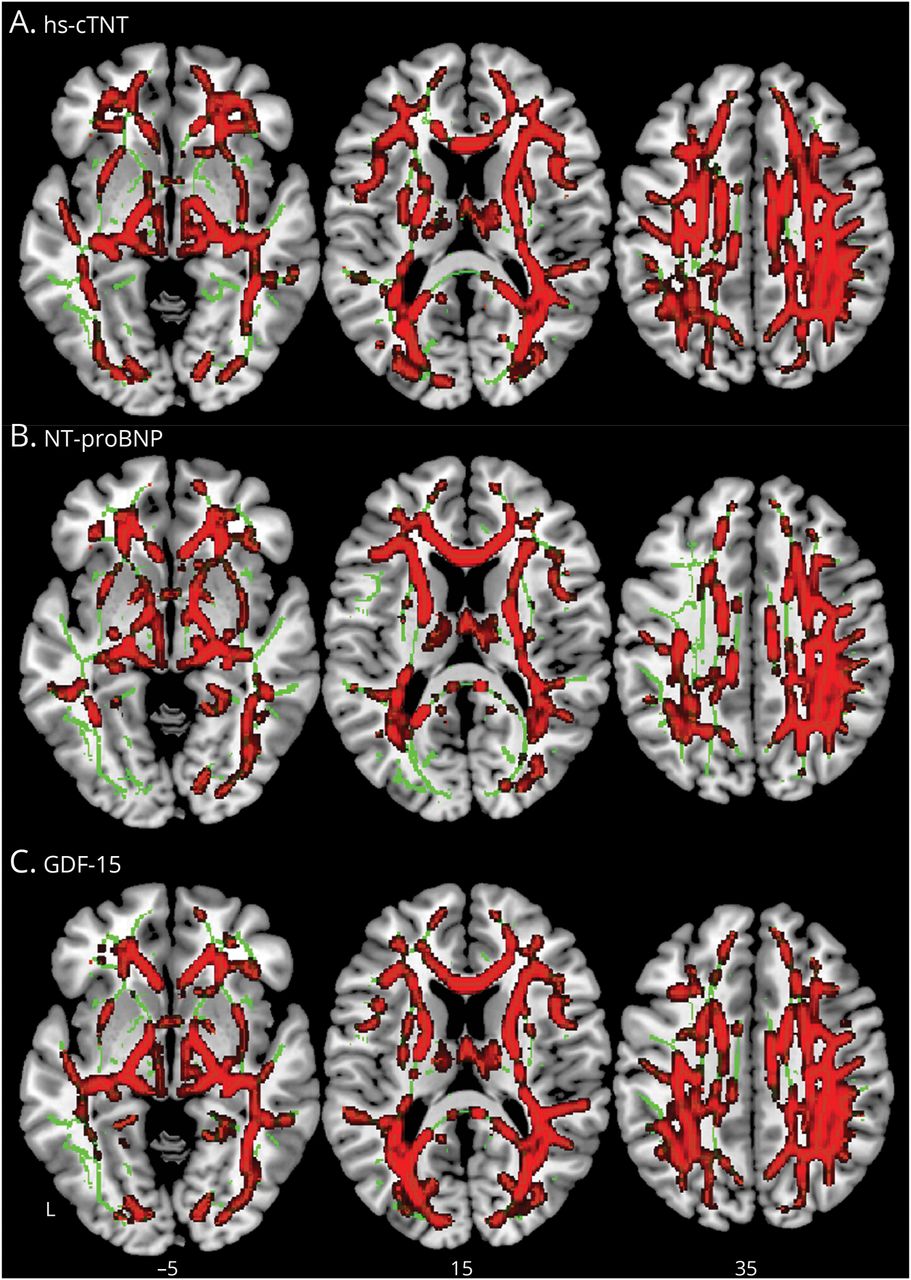

WM FW voxel-wise分析指标表明,更大的心血管生物标志物水平(中位数水平以上病人、hs-cTnT GDF-15)与更高的弗兰克-威廉姆斯在多个WM区域(包括投影、协会、连合、边缘和脑干纤维)在所有CIND和痴呆患者在基线(图2,eTable 5,links.lww.com/WNL/C813)。没有交互效应的认知阶段或CeVD状态等。没有区域显示协会血液生物标志物的WM FW NCI不管CeVD地位。

的整个大脑voxel-wise线性回归表明,更高的弗兰克-威廉姆斯在广泛的脑白质区域值与水平的提高(一)hs-cTNT NTpro-BNP (B)和(C) GDF-15。结果TFCE增强,在报道p< 0.01,FWE纠正。弗兰克-威廉姆斯=自由水;FWE = family-wise错误;GDF-15 15 =增长/分化因素;hs-cTnT =高灵敏度心脏临床;中位数水平以上病人= n端pro激素b型利钠肽;TFCE = threshold-free集群增强。

结果仍然当(1)控制区域WM卷(eFigure 4,links.lww.com/WNL/C813协变量),(2)控制vascular-related (eFigure 4 b),和(3)在正常使用弗兰克-威廉姆斯WM排除地区负责人(eResults)。此外,没有血液协会心血管生物标记和WM组织间脂肪水平。GDF-15,但不是中位数水平以上病人和hs-cTNT相关负责人总额(r= 0.19,95%置信区间0.07 - -0.31,p< 0.05)。